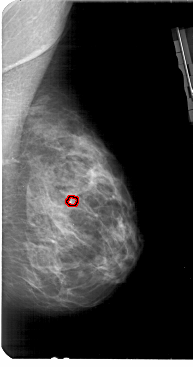

FILE: A_1949_1.RIGHT_CC.OVERLAY

TOTAL_ABNORMALITIES 1

ABNORMALITY 1

LESION_TYPE CALCIFICATION TYPE PLEOMORPHIC DISTRIBUTION CLUSTERED

ASSESSMENT 4

SUBTLETY 3

PATHOLOGY BENIGN

TOTAL_OUTLINES 1

BOUNDARY